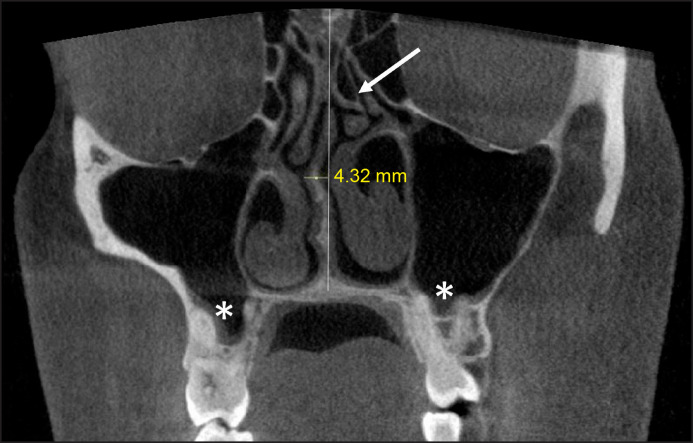

Material and methods: The study included 500 patients aged 18 to 87 years, involving 1000 maxillary sinuses with cone-beam computed tomography scans. We examined the relationship between inferior maxillary pneumatisation and the following anatomic variations: Haller cell, concha bullosa, paradoxical concha, bifid concha, and septal deviation.

Results: Among the 1000 maxillary sinuses assessed, we found 223 (22.3%) with alveolar process pneumatisation (APP), 37 (3.7%) with palatal process pneumatisation (PPP), and 23 (2.3%) with the presence of both APP and PPP. Significant relationships were observed between the Haller cell (P = 0.005), nasal septum deviation (P = 0.000), and middle concha bullosa (P = 0.01) with APP. However, there were no significant relationships between the paradoxical middle concha (P = 0.07), bifid middle concha (P = 0.74), and APP. Similarly, significant relationships were observed between the Haller cell (P = 0.001), paradoxical middle concha (P = 0.009), bifid middle concha (P = 0.000), and PPP. However, there were no significant relationships between concha bullosa (P = 0.799) and PPP. Additionally, we found significant relationships between the Haller cell (P = 0.003) and the presence of both APP and PPP.